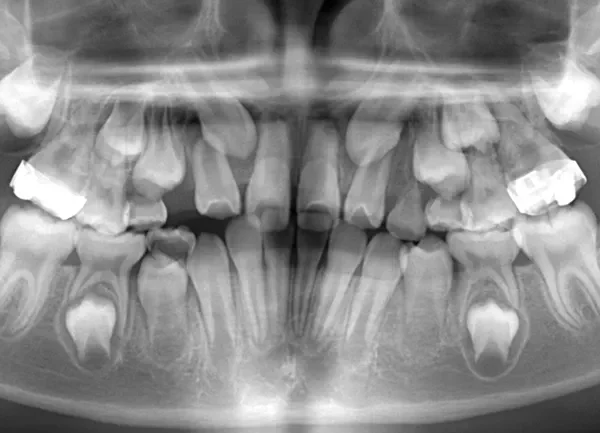

• 治療終了後

治療終了後

先ずは萌出スペースを確保してから開窓術を行い、犬歯を正しい方向へ誘導しました。

マルチブラケット装置は使わずに、最低限の必要な装置を使って目立たないように治療しました。

治療回数29回、2年10ヶ月の治療期間で矯正治療を終了しました。

主訴が改善され、ご満足頂きました。